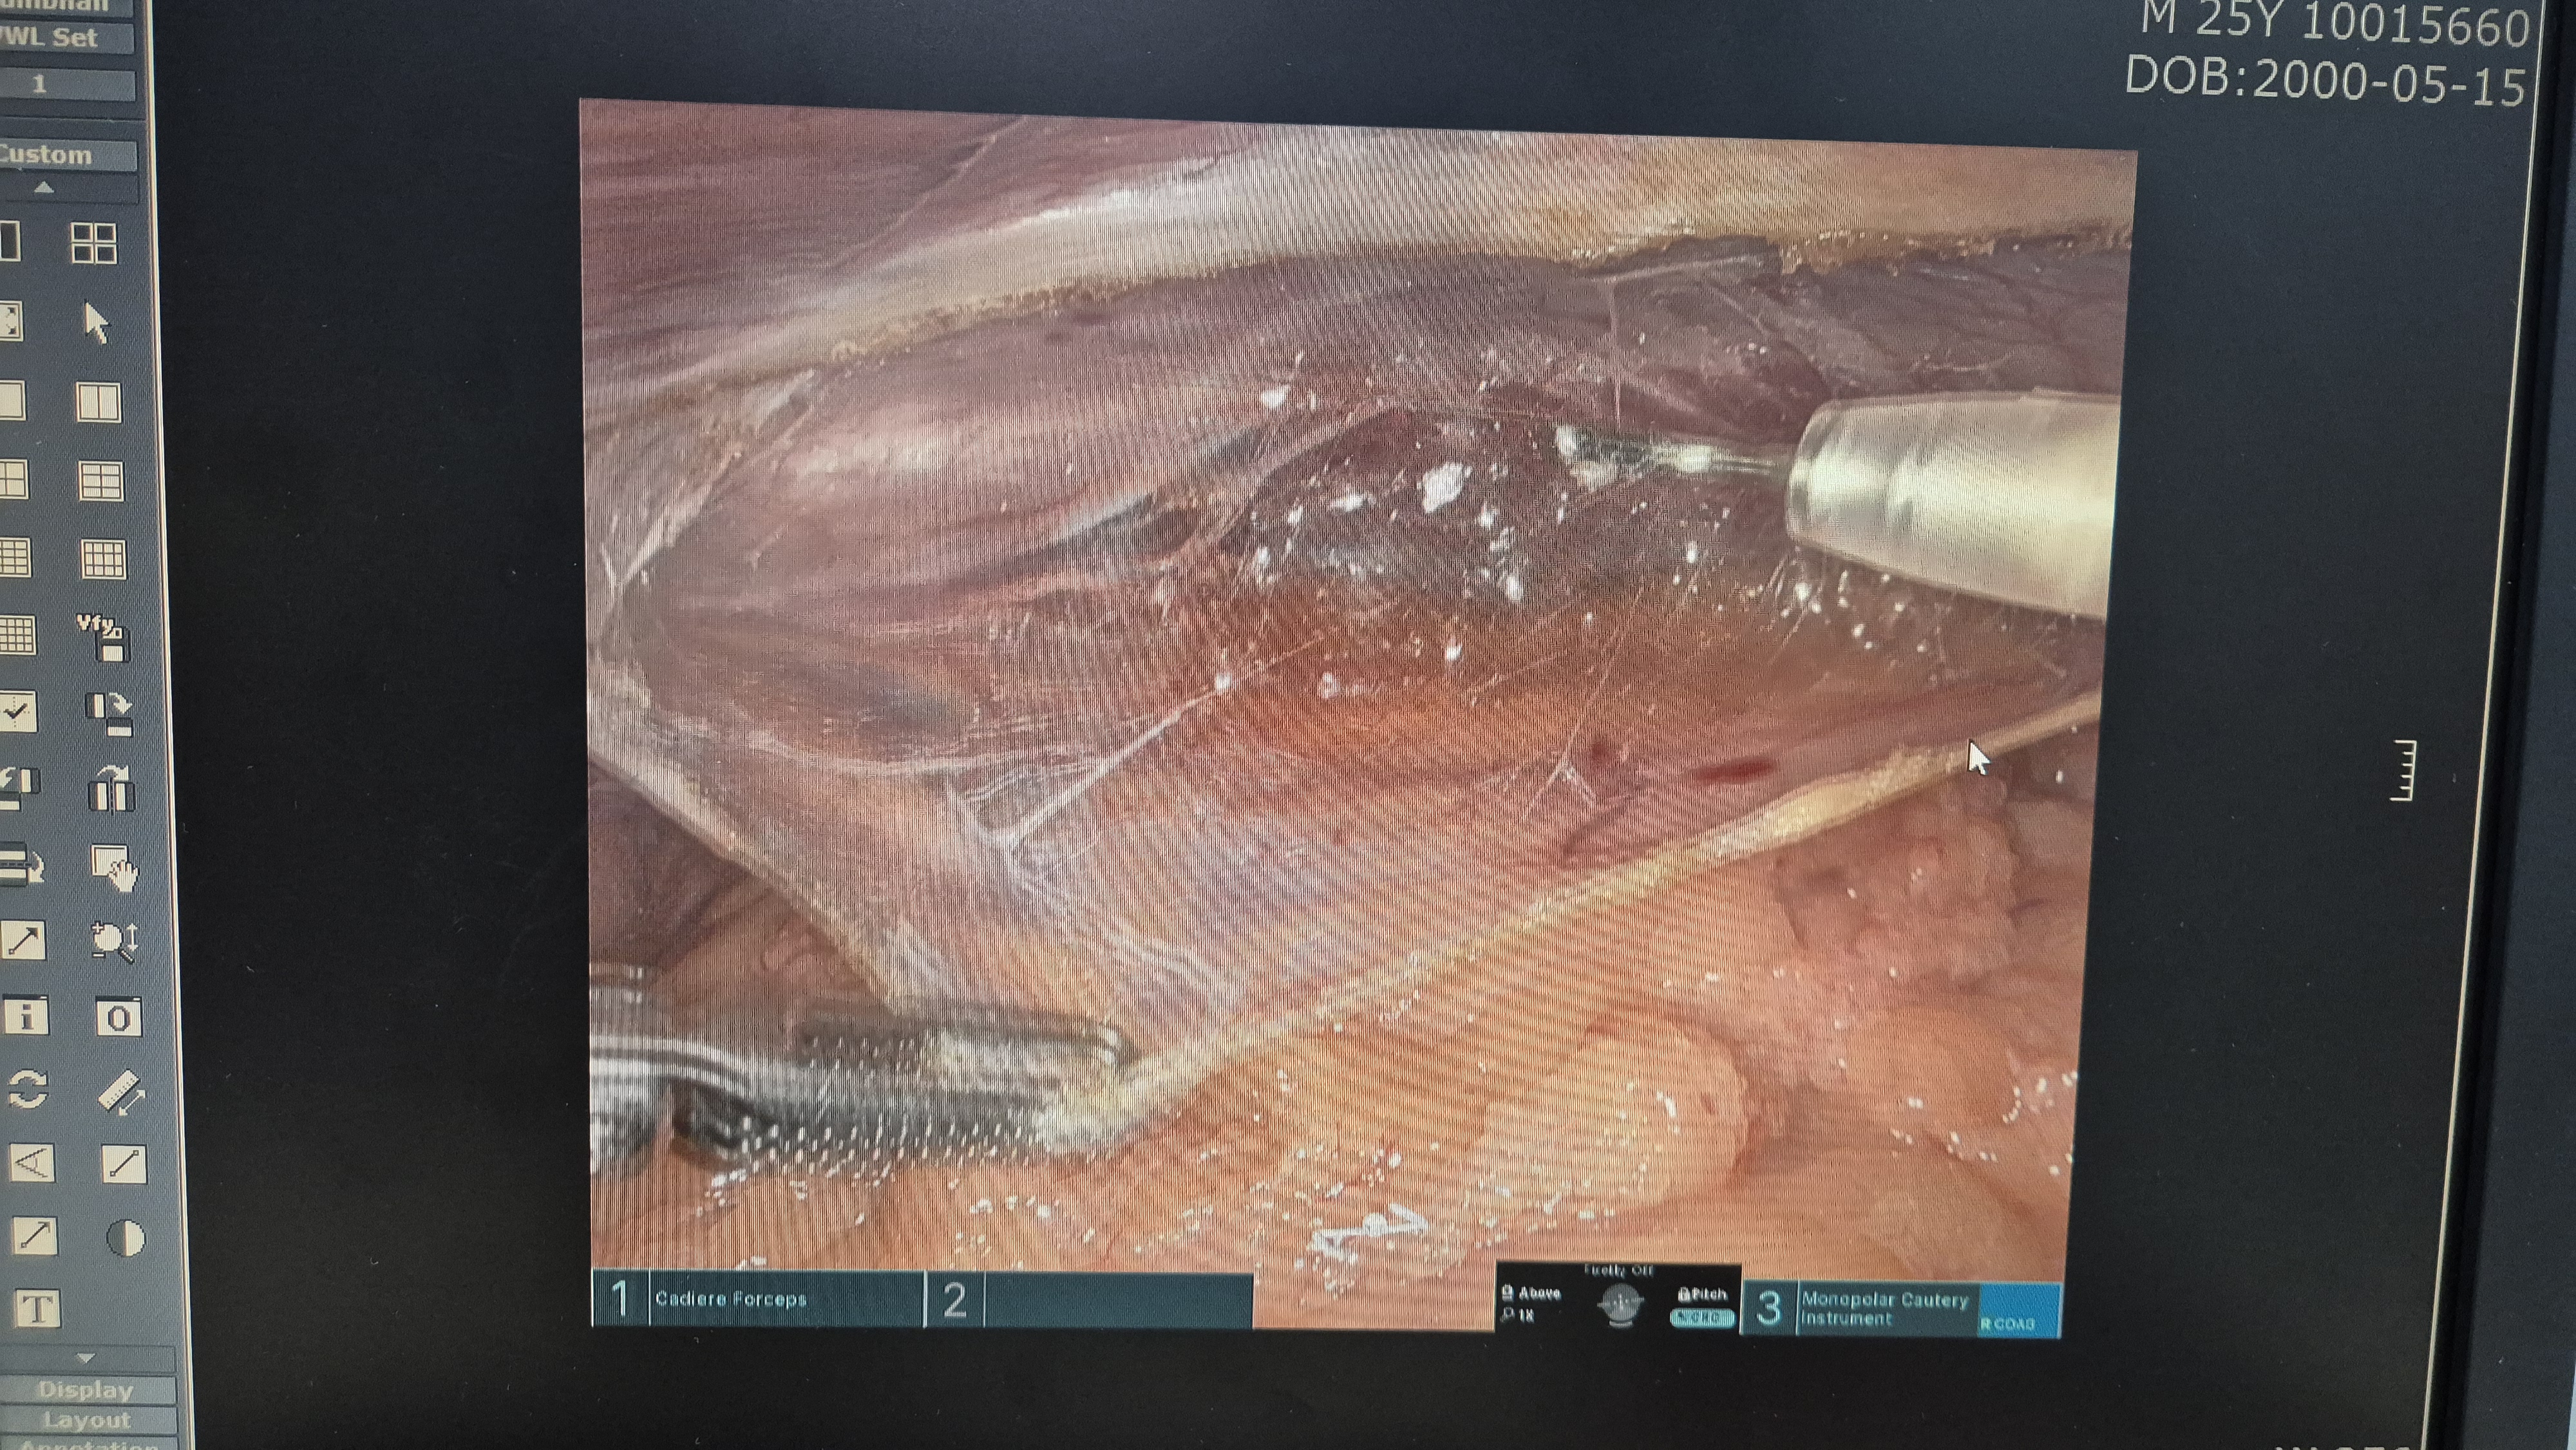

로봇(다빈치sp) 로봇 탈장교정술을 시행했습니다.

감돈된 대망 제거.

복막을 열고.

박리.

메쉬로 고정.

복막봉합.